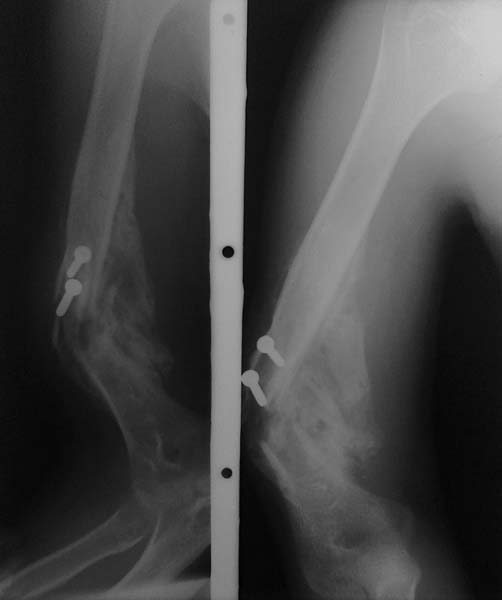

Уважаемые коллеги!  Пациент П 26 лет, на учете у невропатолога по поводу ДЦП. Больной психологический неадеватный. Около 5 мес назад оперирован в одной из ЦРБ по поводу закрытого винтобразного перелома плечевой кости. Произведено открытая репозиция, фиксация отломков компрессирующими винтами. Через 1,5 мес при судорожном приступе упал и получил рефрактуру.

В данный момент имеется выраженная угловая деформация плеча, в проекции деформации-рана 1,5х1,0 см, покрыта коркой, из ран выступает острый конец проксимального отломка (на рентгенограмме видно), отделяемое из ран нет. Потологический подвижность нет. Клинические признаки повреждения лучевого нерва. Помогите определить тактику лечения. Заранее благодарен...